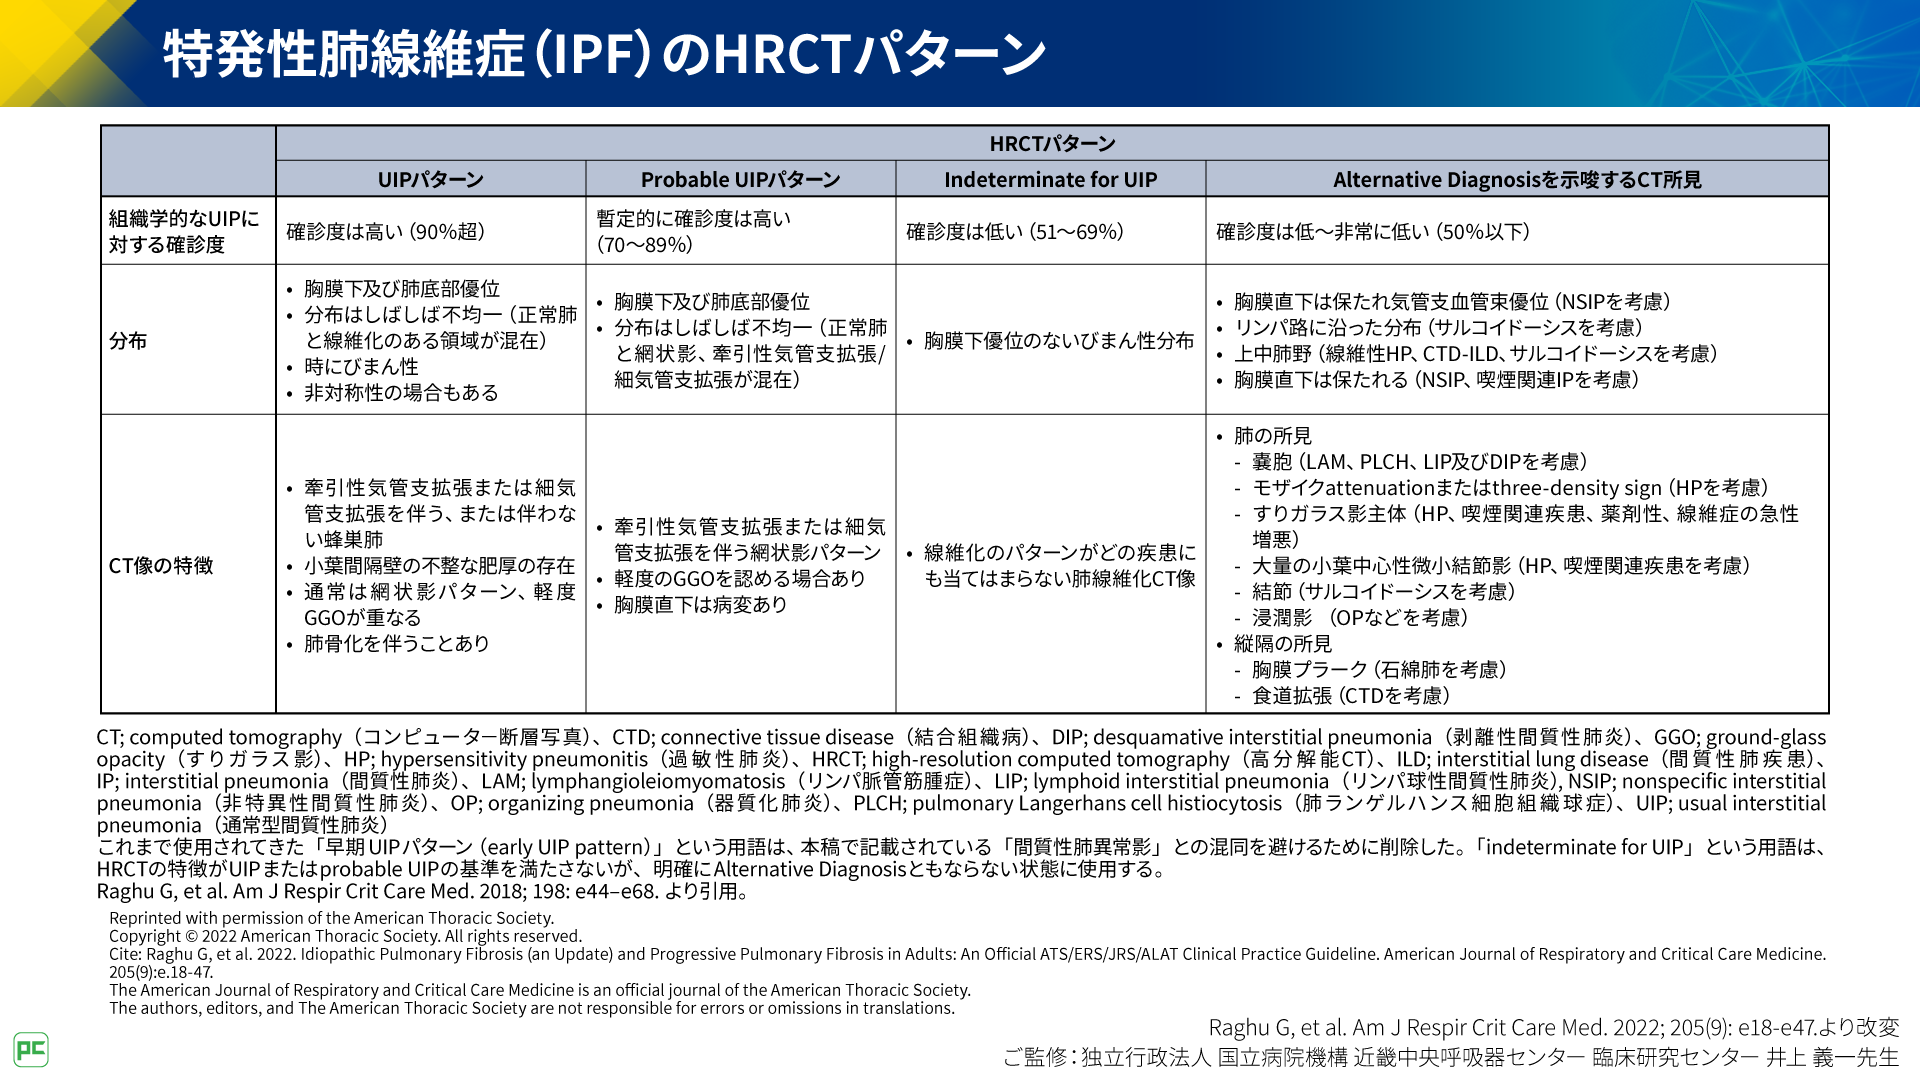

CTパターンから理解する呼吸器疾患 所見×患者情報から導く鑑別と。81Oyrux0rXL._UF350,350_QL50_.jpg。IPFを見逃さないための胸部HRCT画像の読影ポイント(静止画。裁断済みのため全体的に状態が悪いとしています。慢性呼吸不全 (Chronic respiratory failure) – 呼吸器疾患。「CTパターンから理解する呼吸器疾患 所見×患者情報から導く鑑別と治療」門田 淳一定価: ¥ 12000#門田淳一 #門田_淳一 #本 #自然/医療・薬学・健康